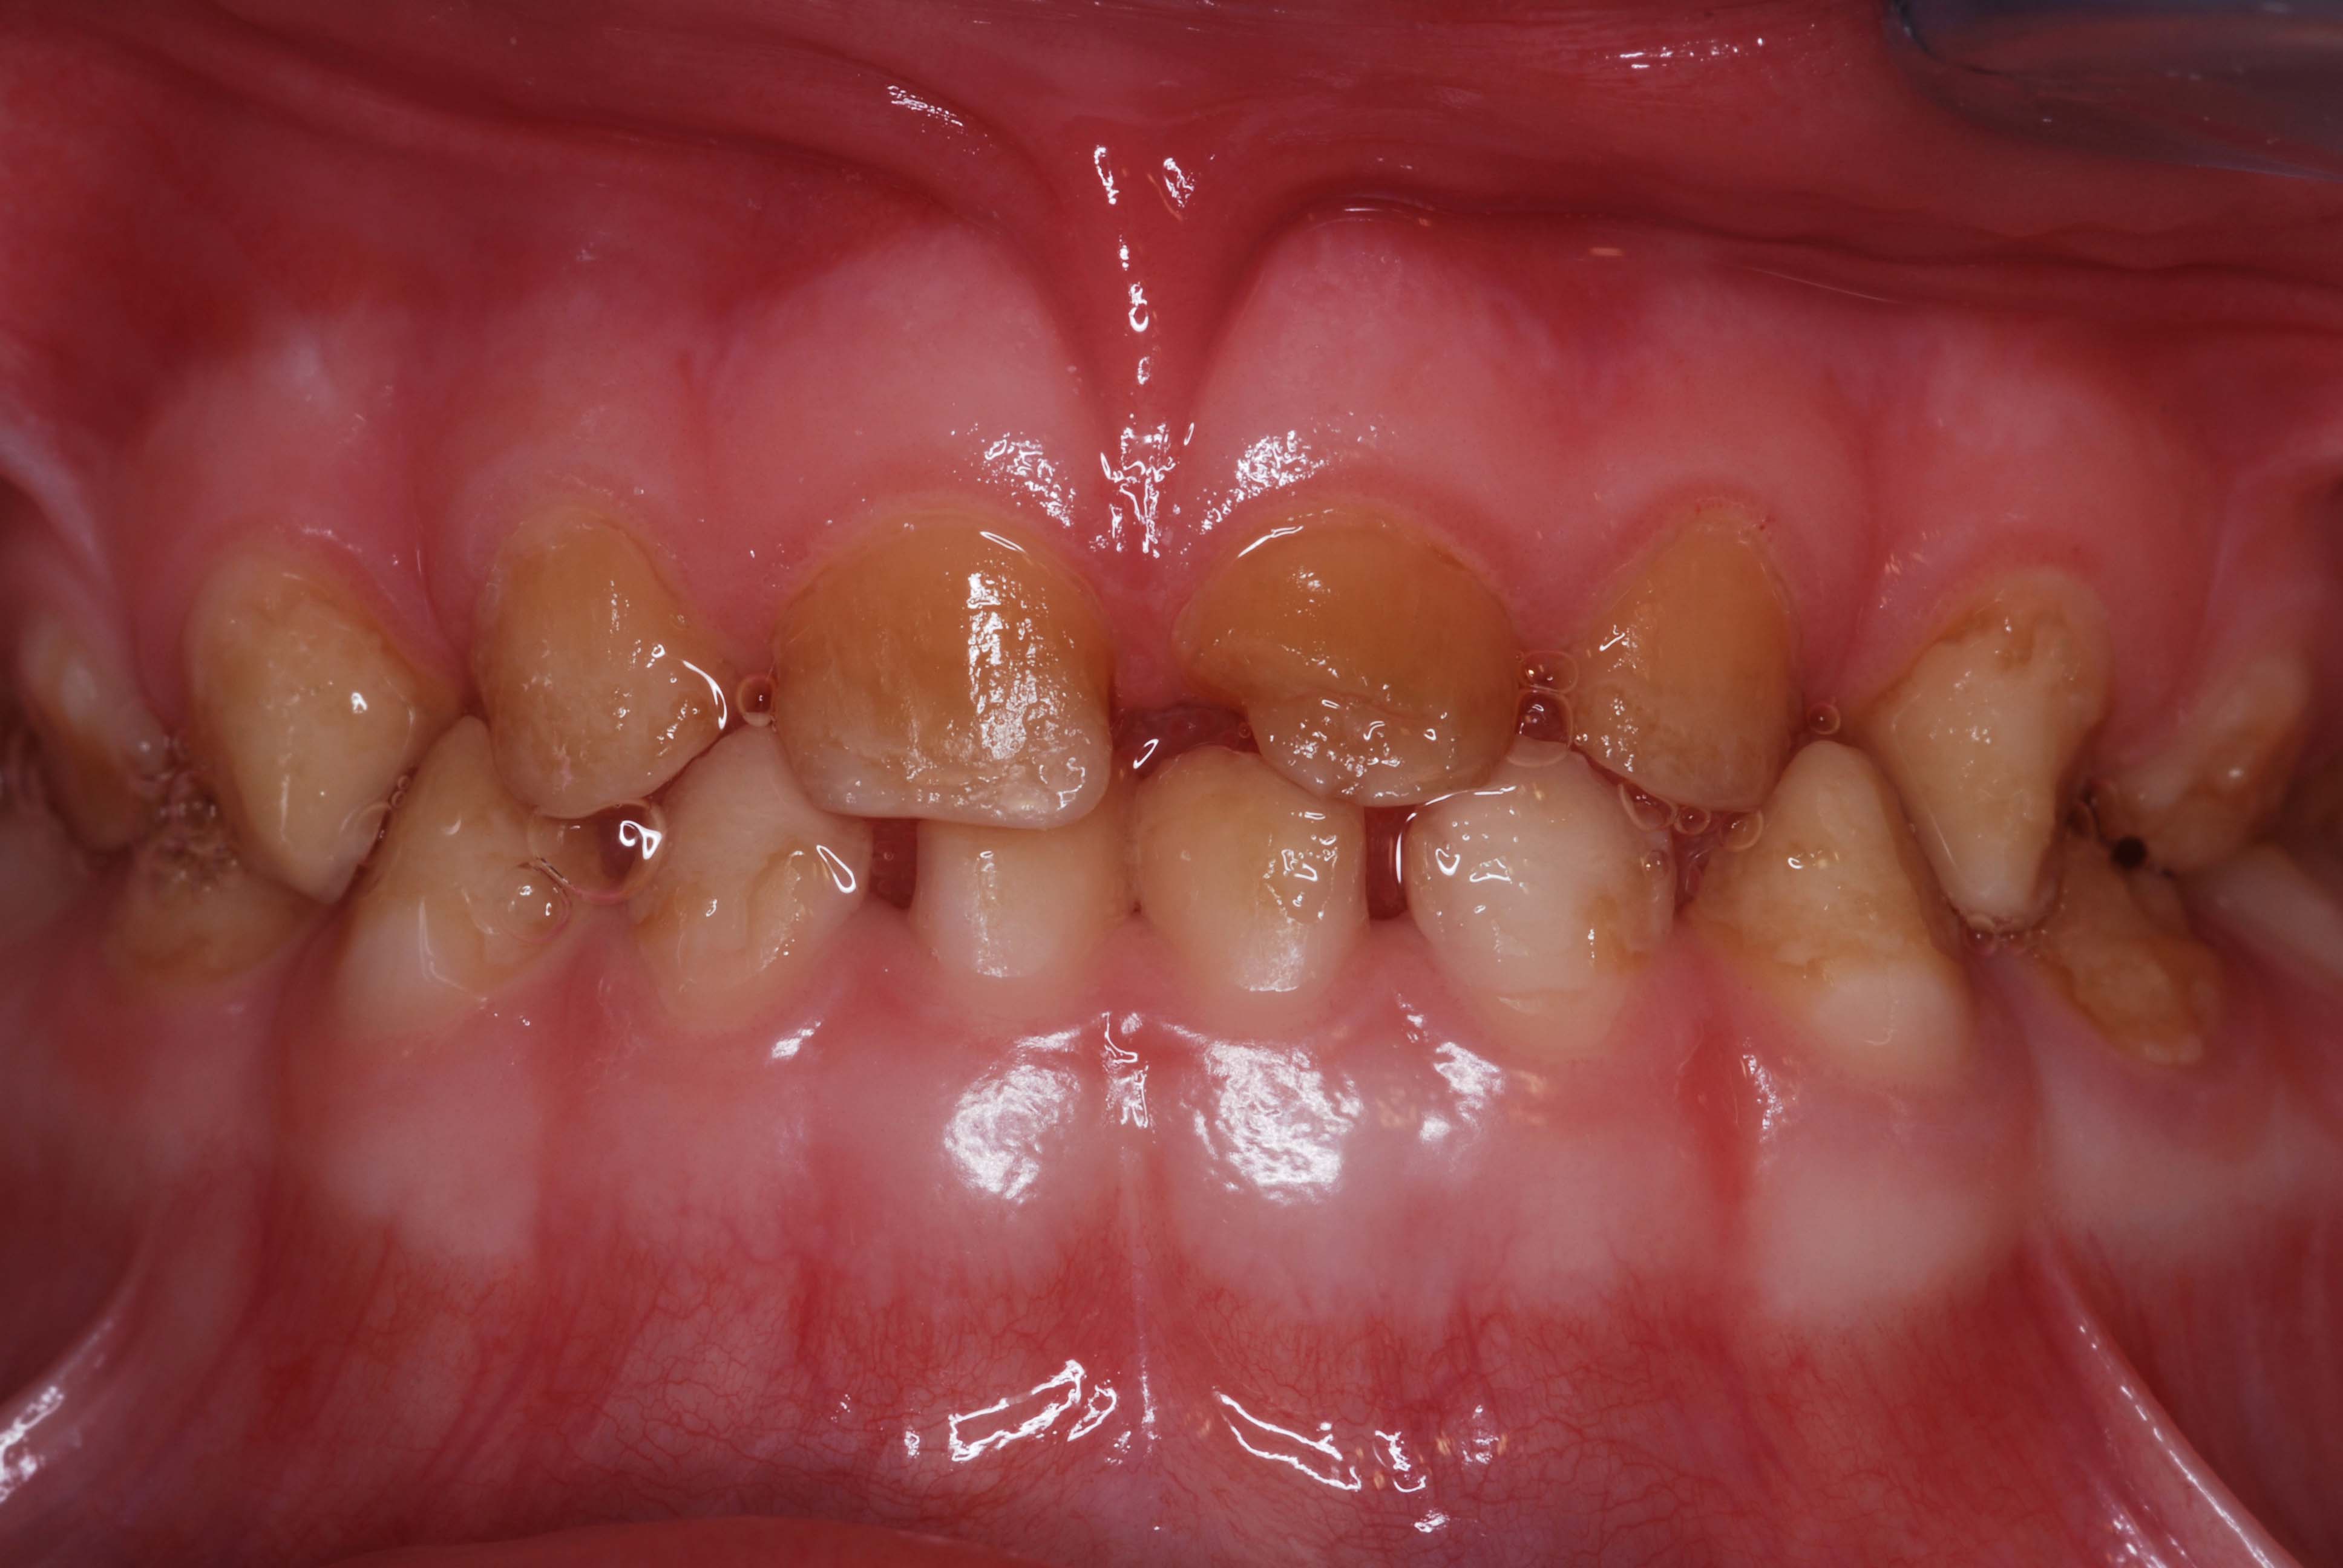

Baby teeth and permanent teeth can both emerge with enamel that is weak improperly formed or missing altogether. It can cause tooth sensitivity and lead to dental caries. There are many reasons why children can present with little or no enamel on their primary teeth baby teeth.

Enamel hypoplasia can be seen in both permanent and baby teeth. Cavities usually appear as brown or black holes in teeth. Sometimes though this incredible protective barrier doesnt develop fully in some children leading to enamel vulnerable to decay and stress fractures from chewing.

Enamel hypoplasia is a defect of the enamel that only occurs while teeth are still developing.

Primary and permanent teeth form at different times and so it is possible that whatever occurred causing enamel hypoplasia on your childs baby teeth will not also be happening during development of their permanent teeth. How Do You Know If You Have No Enamel On Your Teeth. Fluorosis can lead to white or brown spots on the teeth making the surrounding enamel look yellow. Enamel hypoplasia is a developmental defect that results in inadequate enamel. Tooth enamel begins to form before birth and can be affected by the health of the mother and the health of the child after birth. I was also born with no enamel on my teeth. Some of the advice from Moms is. Cavities usually appear as brown or black holes in teeth. Kids with less teeth enamel hypomineralisation need special dental care and diagnosing teeth enamel problems in children at an early age is key to preventing serious teeth problemsCathy Imperial Inspiro oral hygienist who specialises in dental for children talked to us about the issues she finds when checking.

It can affect both baby teeth and permanent teeth. It can cause tooth sensitivity and lead to dental caries. As enamel erodes the edges of teeth become more rough irregular and jagged. I would strongly suggest having a second opinion. Baby teeth are twice as likely to have dental cavities than non-hypoplastic teeth. He will be 4 March 6 and is a wonderful child. The inconvenience and potential harm of this situation is what calls for the immediate attention to this problem.